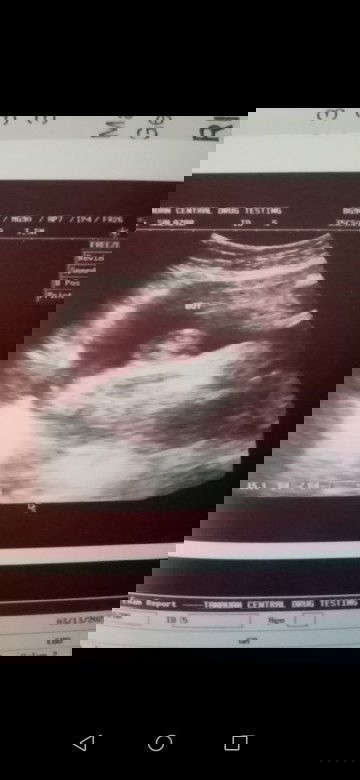

Boy na ba talaga?? 🤔

Una utz qpo is 18 week aq preggy sabi ng sono skn 60% baby boy dw then 2nd utz q is 30 week baby boy parin ang sabi po ng sono skin,.cno po marunong 2mingin ng ultrasound d2 sa palagay nyo po 100% baby boy po ba tlga sya?? Salamat po sa mkksgot